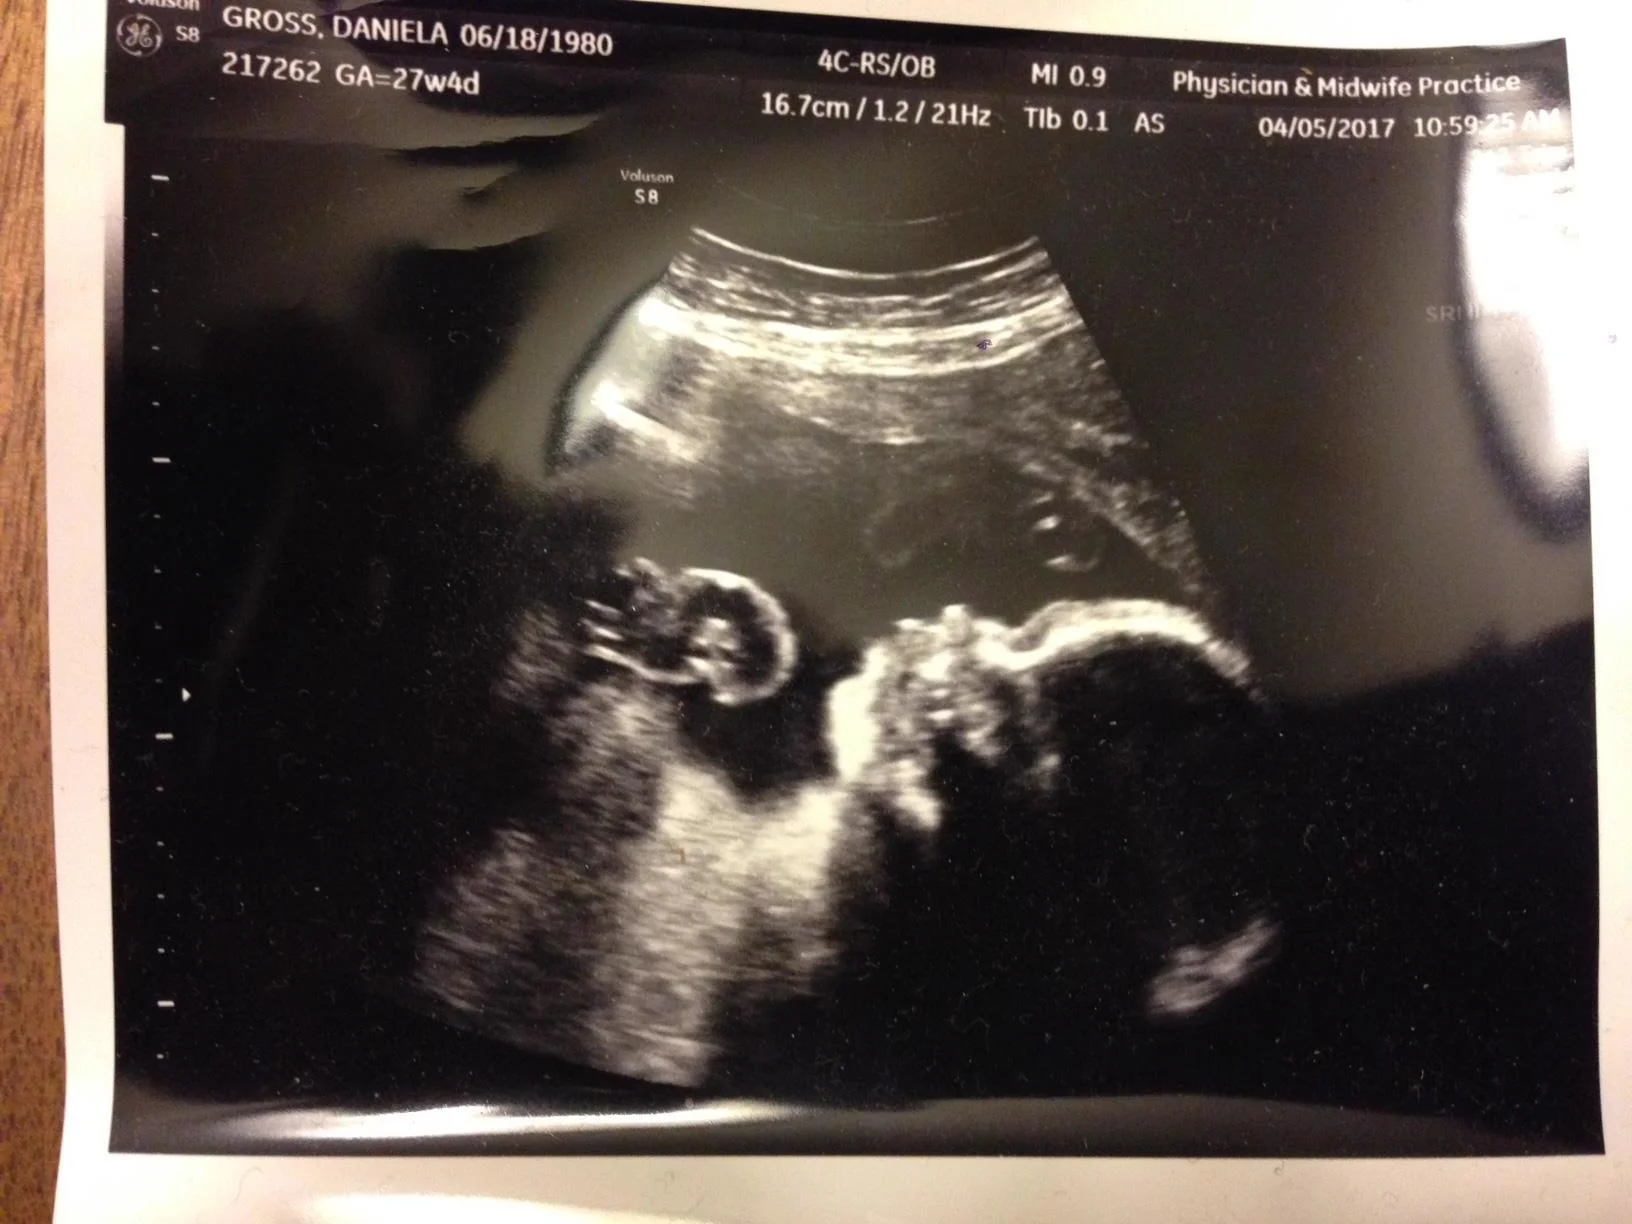

Today we had a scare with Daniela and the baby. When she went to her biweekly check up the doctor noticed that the heartbeat was way to fast, around 180! They told her to go straight to the hospital. Scary and nerve wracking. I left work immediately and met Daniela in the labor/delivery unit of the hospital. It was very nerve wracking. Daniela still has 9 weeks to go. Tadeo cannot be born yet. Finally after 30 minutes Daniela and the baby were observed enough that they determined everything was good. A big relief!!!